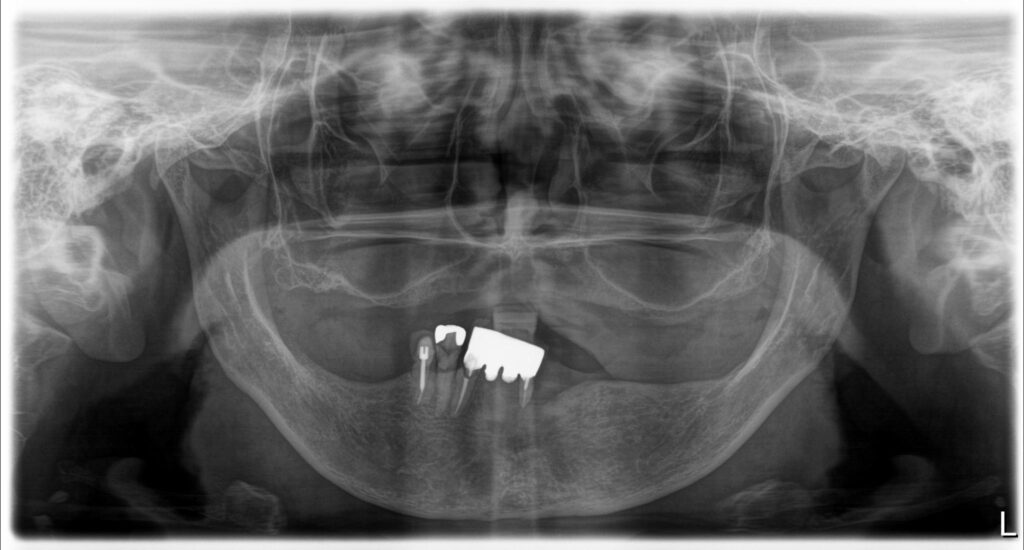

Bedrossianの分類より、ZoneⅠ〜Ⅲいずれにも十分な骨を認めないことから、Insufficient Boneと判断ができ、ノーマルインプラントは困難であることが考えられる。上顎はAll-on-4のためにはザイゴマインプラントが4本必要であることが考えられる。下顎は十分な歯槽骨量があることから、ノーマルインプラント4本を埋入することが可能であると考えられる。また、上顎のザイゴマインプラントの埋入に関しては、 ZAGA分類のType3とType4が混在しているため、ザイゴマインプラントが困難であることが予想される。